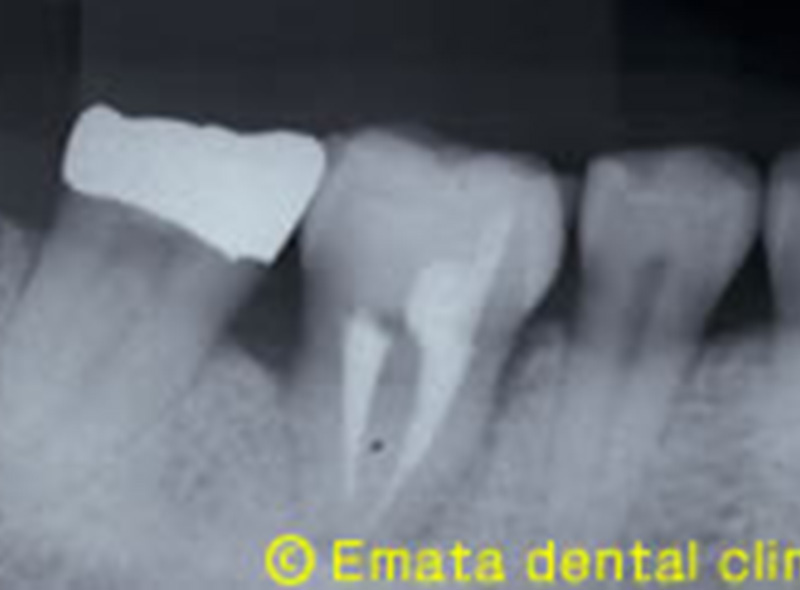

奥歯の自家歯牙移植

Before

After

| 主訴 | 右下の奥歯の抜歯し、親知らずを移植 |

| 治療期間・回数 | 3ヶ月~半年・約8回 |

| 費用 | 150,000円 |

| デメリット・注意点 | 移植ができるかは適用条件による。 |